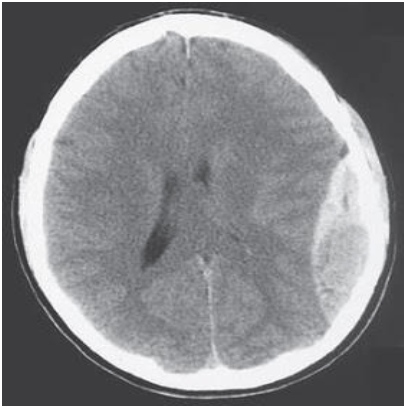

Paciente com traumatismo craniano foi atendido no pronto-socorro e foi realizado o exame a seguir. Qual o diagnóstico?

Fonte: Site Ciência Atual. Disponível em: <www.ciencia-atual.blogspot.com.br/

2009/02/serie-imagem-em-medicina-clinica-20.html>. Acesso em: 25 mar. 2013.